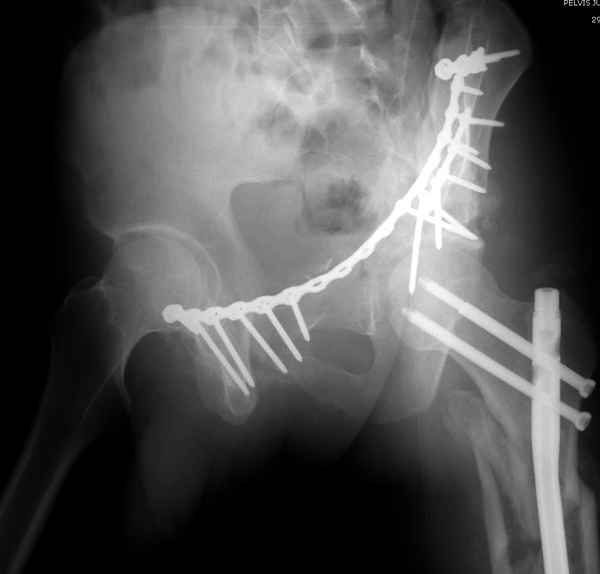

Здесь несколько вариантов двухколонных свежих переломов, которые были оперированы из одного-заднего, а также из двух: переднего и заднего доступов.